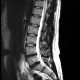

A study published earlier this year suggests that patients who require back surgery are less likely to need further surgery if they have chiropractic treatment. Researchers at University Hospital – Cleveland Medical Center found that patients who received chiropractic spinal manipulation experienced a substantial 45% reduction in the likelihood of undergoing additional lumbar surgery compared to those who received usual medical care. Specifically, the proportion of patients undergoing lumbar spine reoperation was 7% in the chiropractic spinal manipulation group, significantly lower than the 13% in the usual medical care group. It is important to note, however, that the patients included in the study had a very specific type of surgery: discectomy. That is, the removal of part of the disc. Patients who had more involved surgery that required instrumentation, like lumbar fusion, were not included. As always, more work is needed to establish these conclusions. But these impressive findings suggest that even patients who have had back surgery may benefit from chiropractic treatment.